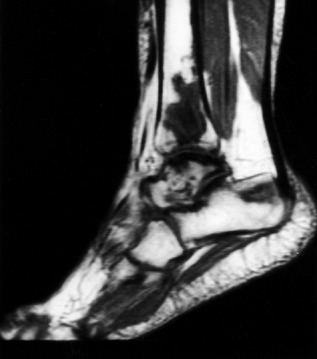

areas will also develop symptomatic osteonecrosis. These include knees,

shoulders, wrists, feet, and, rarely, elbows and facial bones.

Accordingly, these areas should be evaluated by history and physical

examination. If there is any question of involvement, plain radiographs

and perhaps a bone scan or an MRI should be obtained. Recently, MRI

studies have indicated that the incidence might be considerably higher

than expected.